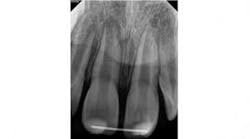

At three months, the clinical testing was equivalent and radiographs showed a fracture still present, but the periodontal ligament (PDL) and lamina dura (LD) were intact and uniform, especially near the fracture line (figure 2). At six months, there was no change in the response to vitality testing and radiographs continued to show no deleterious changes (figure 3).